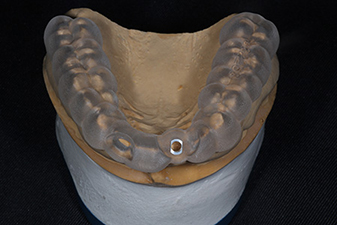

インプラントは3つのパーツから構成されます。

このインプラントの土台部分の形は、インプラントのネジの位置により大きく制限を受けます。

このX線写真のようにネジの位置が適切であれば、土台の移行部がなだらかで磨きやすい形と言えますが、このネジの位置が浅かったり、土台に急な角度がついてしまうとご自身でのブラッシングが困難になります。